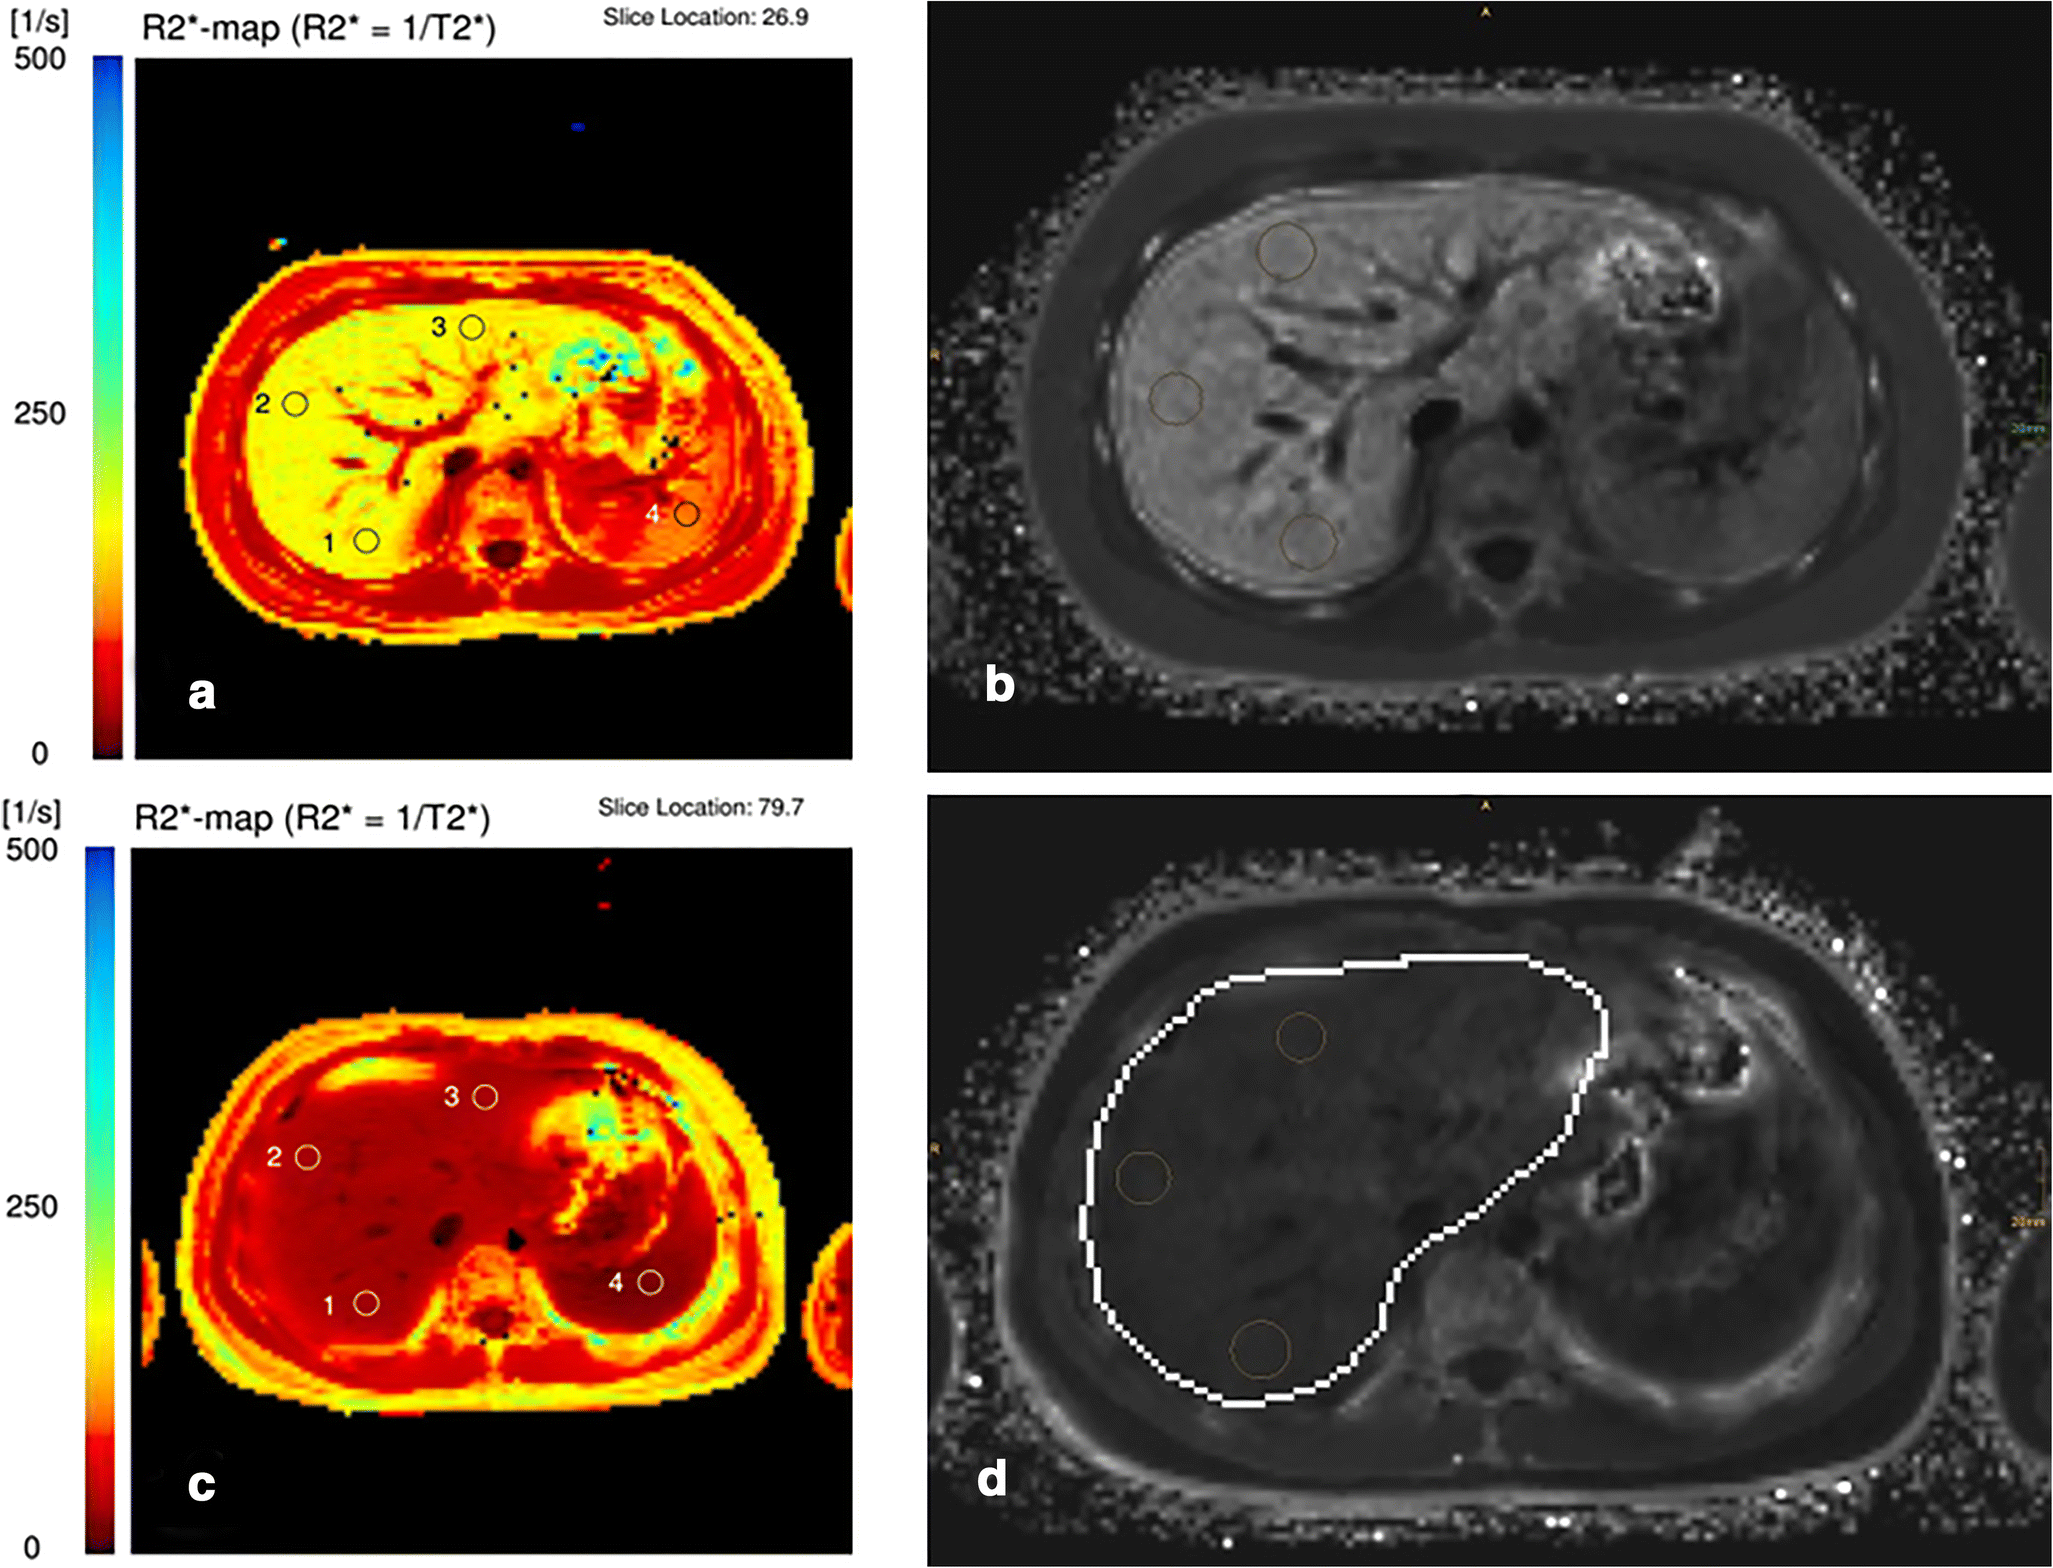

Liver iron quantification using T2* (a) and R2* (b) maps in a patient Liver Iron Quantification Mri This article is a guide for. Based on this summary, expert consensus panel. There are two principle methods of liver iron quantification by mri: While detection of liver iron using qualitative mri is possible, qualitative mri methods do not. This review describes mr imaging techniques for liver iron quantification and provides an overview of. Advanced mr imaging for quantification of. Liver Iron Quantification Mri.

Quantification of liver iron concentration by MRI. (A) Important Liver Iron Quantification Mri T2 relaxometry and signal intensity ratio. Advanced mr imaging for quantification of liver iron. Detection and quantification of liver iron content. This review describes mr imaging techniques for liver iron quantification and provides an overview of. This article is a guide for. While detection of liver iron using qualitative mri is possible, qualitative mri methods do not. There are two. Liver Iron Quantification Mri.